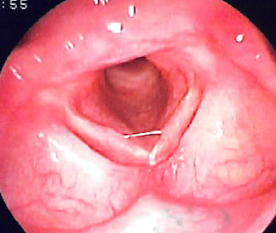

声帯溝症

左右の声帯に溝(ミゾ)ができ、声帯粘膜が振動できず、声がかすれ出しにくくなります。

左右の声帯に溝(ミゾ)ができ、声帯粘膜が振動できず、声がかすれ出しにくくなります。